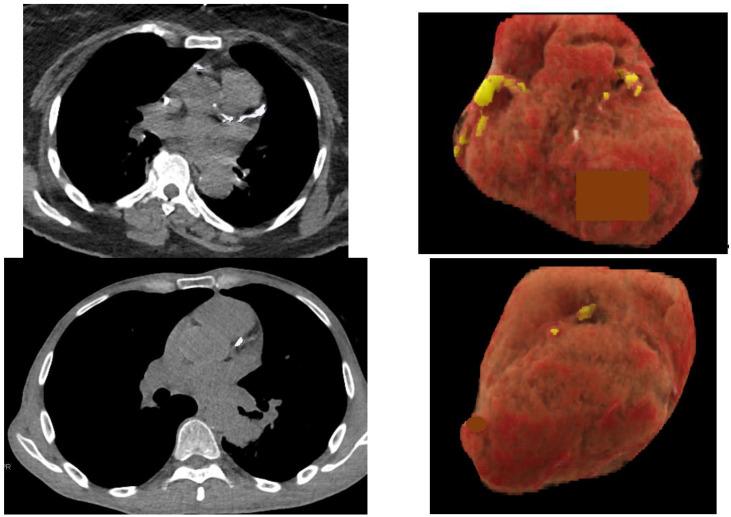

Two large randomized controlled trials of low-dose CT (LDCT)-based lung cancer screening (LCS) in high-risk smoker populations have shown a reduction in the number of lung cancer deaths in the screening group compared to a control group. Even if various countries are currently considering the implementation of LCS programs, recurring doubts and fears persist about the potentially high false positive rates, cost-effectiveness, and the availability of radiologists for scan interpretation. Artificial intelligence (AI) can potentially increase the efficiency of LCS. The objective of this article is to review the performances of AI algorithms developed for different tasks that make up the interpretation of LCS CT scans, and to estimate how these AI algorithms may be used as a second reader. Despite the reduction in lung cancer mortality due to LCS with LDCT, many smokers die of comorbid smoking-related diseases. The identification of CT features associated with these comorbidities could increase the value of screening with minimal impact on LCS programs. Because these smoking-related conditions are not systematically assessed in current LCS programs, AI can identify individuals with evidence of previously undiagnosed cardiovascular disease, emphysema or osteoporosis and offer an opportunity for treatment and prevention.

两项针对高危吸烟人群进行的基于低剂量CT(LDCT)的肺癌筛查(LCS)大型随机对照试验表明,与对照组相比,筛查组的肺癌死亡人数有所减少。尽管目前各国都在考虑实施LCS计划,但对于潜在的高假阳性率、成本效益以及放射科医生进行扫描解读的可用性,仍存在反复的疑虑和担忧。人工智能(AI)有可能提高LCS的效率。本文的目的是回顾为构成LCS CT扫描解读的不同任务而开发的AI算法的性能,并估计这些AI算法如何用作第二阅片者。尽管LDCT的LCS降低了肺癌死亡率,但许多吸烟者死于与吸烟相关的合并症。识别与这些合并症相关的CT特征可以在对LCS计划影响最小的情况下提高筛查价值。由于目前的LCS计划中没有系统地评估这些与吸烟相关的情况,AI可以识别出有先前未诊断出的心血管疾病、肺气肿或骨质疏松症证据的个体,并提供治疗和预防的机会。